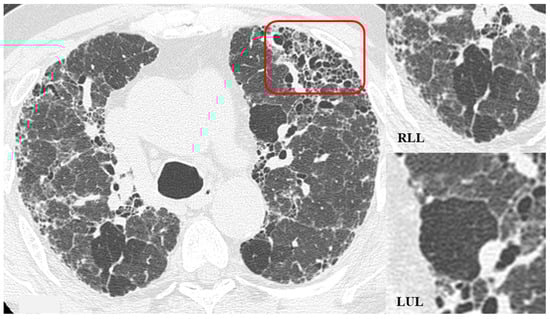

Figure 6.

HRCT of the chest and magnification areas of RLL and LUL in FHP. Three-density pattern with lobular areas of reduced attenuation in both lungs (magnification images), overlapping with areas of increased density where distinct fibrotic alterations are evident, characterized by intra- and inter-lobular thickening with traction bronchiectasis and bronchiolectasis (red box). In certain patients, the absence of typical HRCT fibrotic features leads to their classification as “pattern compatible with FHP”. Suggestive elements of this pattern are fibrosis with a mixed central and peripheral distribution (Figure 7) and the fibrotic pattern with basal predominance (Figure 8).